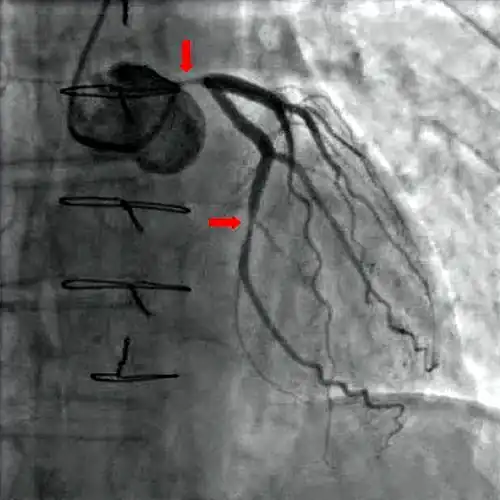

Koronarangiografie: Dargestellt wird die linke Koronararterie mit ihren Ästen.

Koronarangiografie partieller Okklusionen der linken Koronararterie und der seitlichen Kranzarterie (Arteria circumflexa) (siehe Pfeile).[23]

Mit Hilfe der diagnostischen Koronarangiographie können Koronararterien dargestellt und deren Anatomie sowie das Ausmaß und die Lokalisation eventueller Stenosen beurteilt werden. Sie ist die Untersuchung mit der besten Aussagekraft. Bei dieser Untersuchung wird ein Herzkatheter über die Arteria femoralis (Oberschenkelarterie) oder seltener über die Arteria brachialis (Oberarmarterie) bis zu den Abgängen der Koronararterien aus der Aorta vorgeschoben und Kontrastmittel in die Abgänge injiziert. Mit Hilfe von Röntgenstrahlung können die Koronararterien sichtbar gemacht und beurteilt werden.[24] Der Katheter kann, unter Überbrückung der Aortenklappe, weiter in die linke Herzkammer vorgeschoben werden. Diese Untersuchung wird als Ventrikulografie bezeichnet. Sie ermöglicht zusätzlich regionale Kontraktionsstörungen sichtbar zu machen, die zum Beispiel Hinweise auf zurückliegende Herzinfarkte bieten können, sowie eine Beurteilung der linksventrikulären Pumpfunktion über Berechnung der Auswurffraktion und die Bestimmung der Dehnbarkeit der Herzmuskulatur (Compliance) durch Bestimmung des enddiastolischen Volumens.[1]